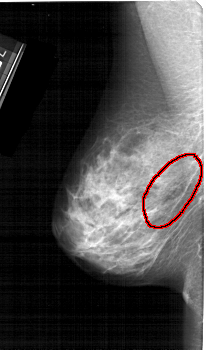

A_1391_1.LEFT_MLO

LEFT_MLO LINES 5236 PIXELS_PER_LINE 3076 BITS_PER_PIXEL 12 RESOLUTION 43.5 OVERLAY

FILE: A_1391_1.LEFT_MLO.OVERLAY

TOTAL_ABNORMALITIES 1

ABNORMALITY 1

LESION_TYPE CALCIFICATION TYPE PLEOMORPHIC DISTRIBUTION SEGMENTAL

ASSESSMENT 4

SUBTLETY 4

PATHOLOGY BENIGN

TOTAL_OUTLINES 1

BOUNDARY